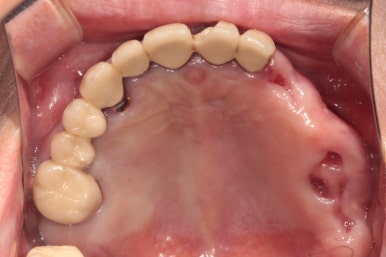

입천장쪽에서 바라 보았을 때 왼쪽 위 어금니는 뿌리만 남아 발치하였습니다.

아래턱은 보시다시피 치아가 5개 밖에 남지 않았어요.